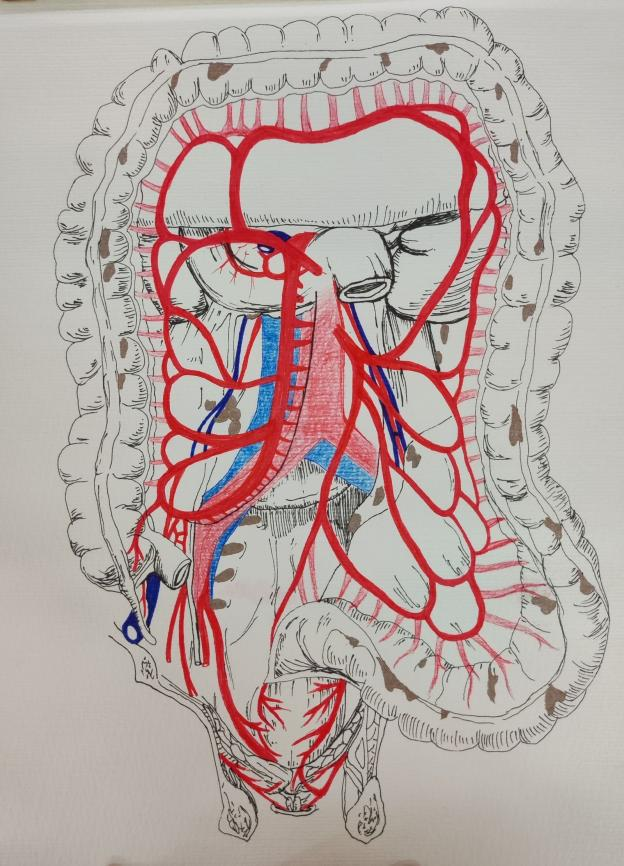

马文琪《肠系膜上动静脉的供血》